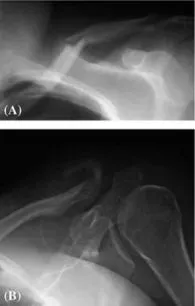

The shoulder girdle consists of three bones and two joints: the scapula, the clavicle, and the proximal humerus, as well as the glenohumeral and acromioclavicular joints. Most fractures of the clavicle occur either in the midshaft or the distal end, mainly because the coracoclavicular ligament is fan shaped and is rather strong, so the fractures occur at either side of this (Fig. 1A, B).

Figure 1 (A) There is a midshaft fracture of the clavicle with some angulation. (B) There is a fracture of the distal clavicle with evidence of motion.